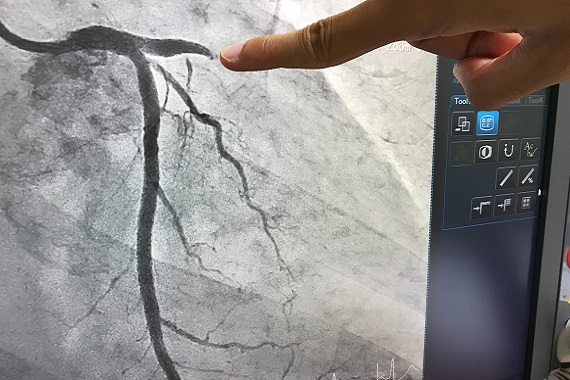

Surgeons carrying out an angiogram

A heart attack happens when there is a blockage in one of the coronary arteries that supply blood to the heart. If a complete blockage is suspected – called a ‘STEMI’ heart attack – doctors will usually perform an X-ray procedure called a coronary angiogram to look for blockages. Based on the findings at angiogram, the blocked artery can either be physically opened up with a balloon and stent (angioplasty), or bypassed using pieces of arteries or veins (coronary artery bypass surgery).